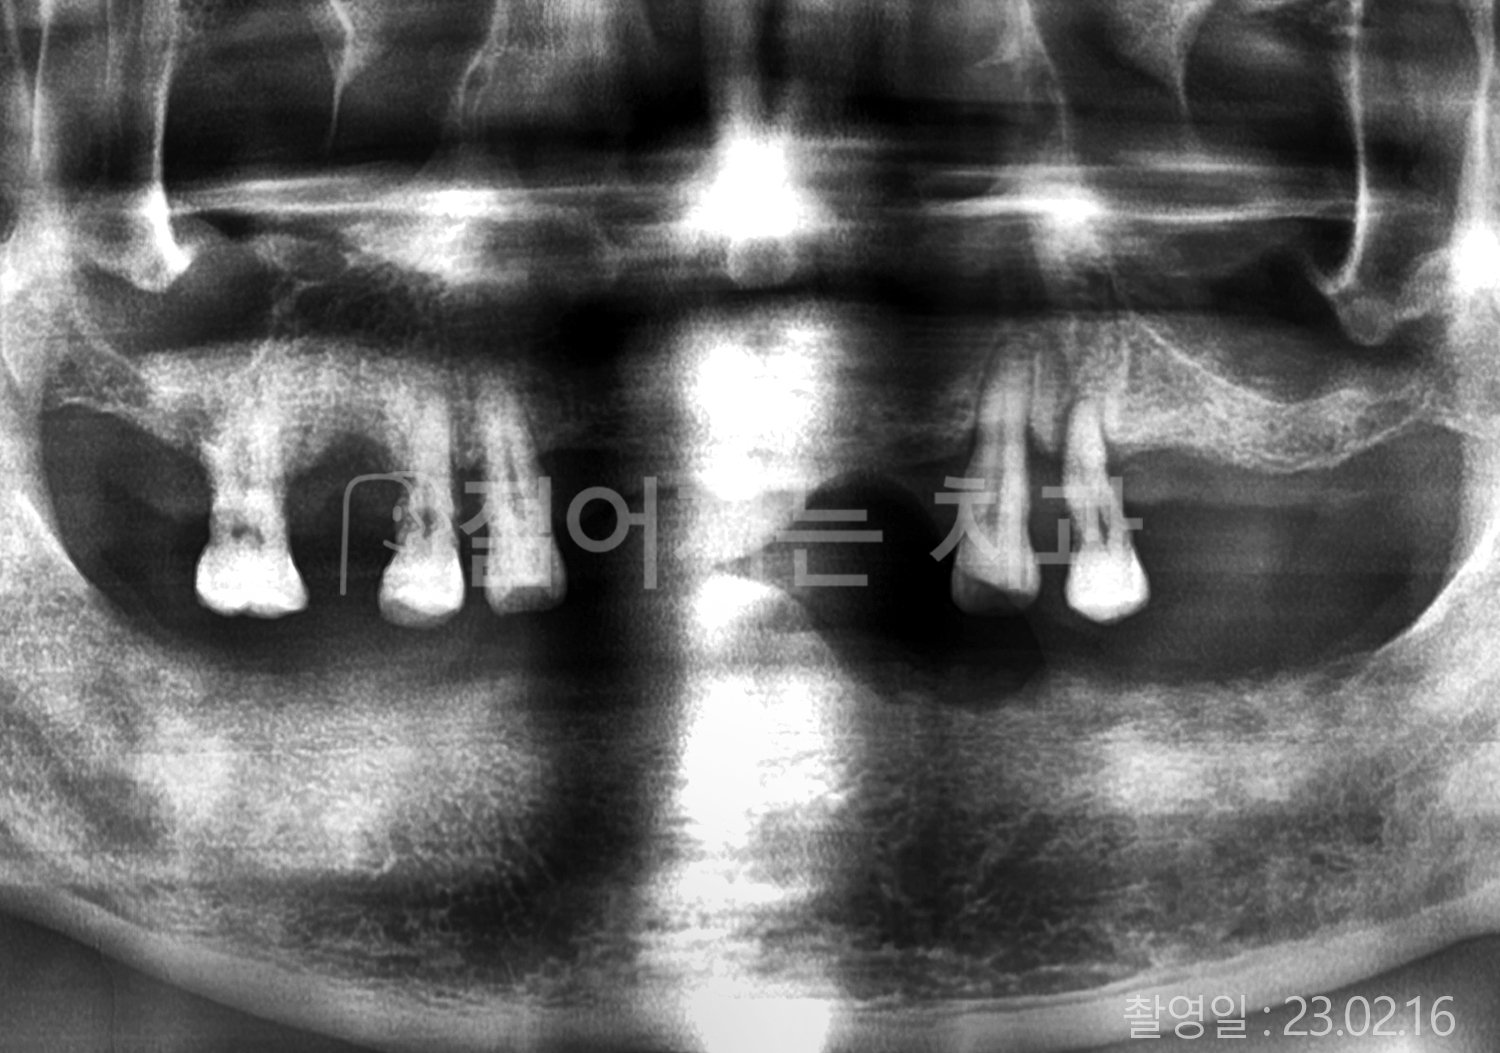

• 70대 고혈압, 고지혈증 전체치아 10개 이상 임플란트

• 60대 당뇨, 간염 전체치아 10개 이상 임플란트

• 80대 골다골증 전체치아 6개 이상 임플란트

• 70대 고혈압, 당뇨 전체치아 10개 이상 임플란트

• 60대 간 질환 전체치아 10개 이상 임플란트

• 60대 전체치아 10개 이상 임플란트

• 70대 전체치아 10개 이상 임플란트

• 50대 전체치아 10개 이상 임플란트

• 60대 고혈압, 고지혈증 전체치아 10개 이상 임플란트

• 40대 고지혈증, 뇌혈관 질환 전체치아 10개 이상 임플란트